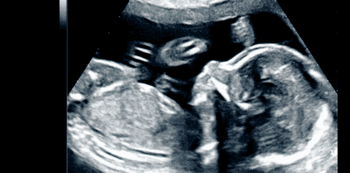

Baby COVID-19 positive inside womb, naitala ang unang kaso sa Texas. Bagama’t wala pang matibay na mga pruweba na napapasa ang COVID mula sa ina to newborn ay hindi pa rin maaalis ang posibilidad nito.

Baby COVID-19 positive inside womb

Dalawang araw pa lamang pagkapanganak ng sanggol na nag-positibo ay nakitaan na siya ng mga sintomas ng COVID. Ito ay dahil umano sa utero transmission, kung saan nahawa ang sanggol sa kanyang ina na nagpositibo.

Ayon sa pag-aaral, nagmula sa placenta ng ina ang virus. Ito kasi ang target ng virus sa katawan ng buntis. Napag-alaman din na may pamamaga sa tissue at proteins na indikasyon din ng COVID sa buntis.